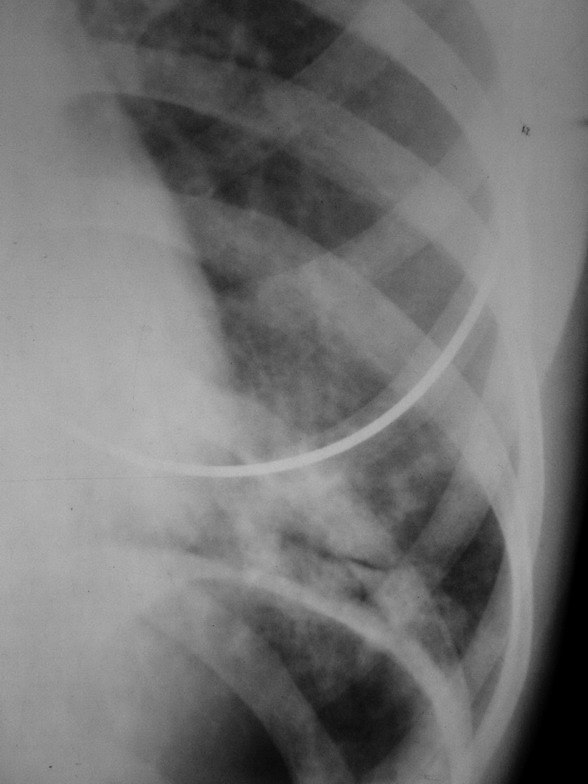

患者 女 22岁 咳嗽 咳痰 体温37.4度 白细胞在正常范围 于十日前诊断左肺下炎症 在个体诊所抗炎治疗9日 用药不详(未做过敏实验)今日复查 该患半年前曾在外院诊断过左肺下炎症 后治愈 该患者体质瘦弱

十日前片: